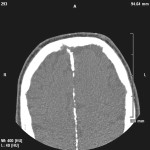

Aspetti clinici, genetici e terapeutici della sindrome di Gorlin Goltz

Aspetti clinici, genetici e terapeutici della sindrome di Gorlin Goltz: revisione della letteratura e descrizione di un caso clinico rappresentativo